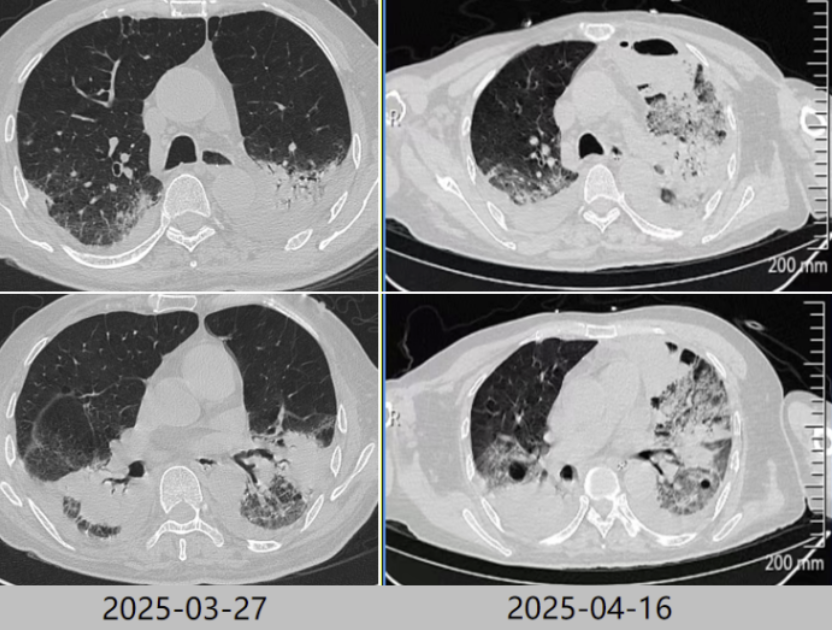

根据病原学结果,先后予以米卡芬净+美罗培南、哌拉西林他唑巴坦+环丙沙星、头孢他啶阿维巴坦抗感染治疗。2025年3月24日拔管。3月27日复查胸部CT提示肺部病变好转吸收(图5)。患者仍有明显咳痰困难,乏力,四肢肌力下降,经康复锻炼恢复欠佳。

图5 复查胸部CT对比